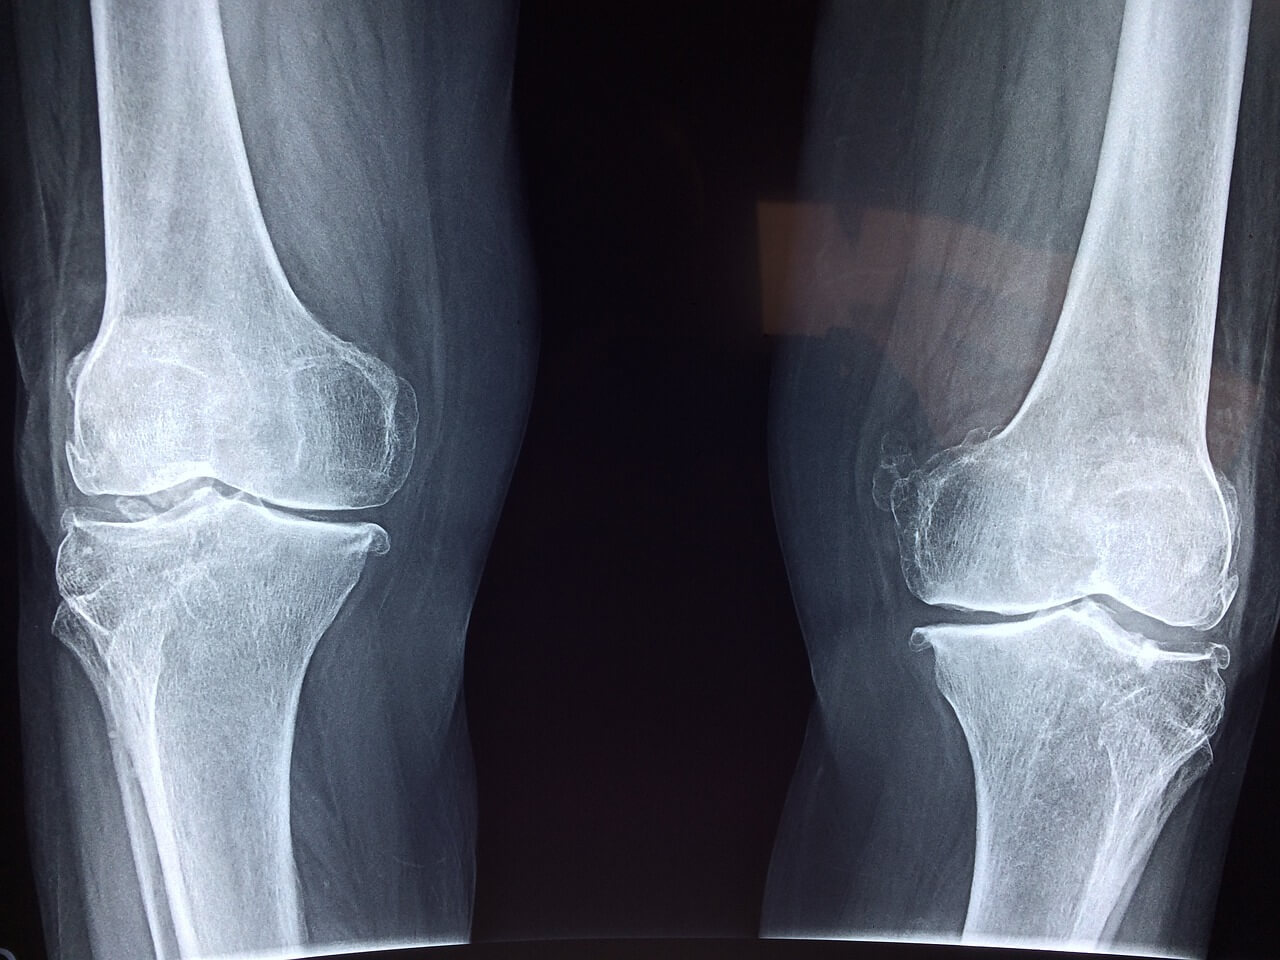

1️⃣ 무릎인공관절 로봇수술 평균 비용

✅ 무릎인공관절 로봇수술 비용은 일반 수술보다 조금 더 높은 편이에요.

평균적으로 보면, 일반 인공관절 수술: 200~300만 원대 (건강보험 적용 후 본인부담)

● 로봇 인공관절 수술: 약 400만 원~600만 원대 (추가 비용 포함)

✅ 로봇수술 비용 중 **'로봇 사용료'는 비급여 항목**이기 때문에 병원마다 금액이 다를 수 있어요. 일반적으로 150만 원~250만 원 정도의 로봇 추가 비용이 발생합니다.

✅ 한쪽 무릎만 할 경우와 양쪽을 동시에 수술할 경우에도 비용이 크게 달라질 수 있으니, 병원비 정보 공개 사이트에서 미리 병원별 평균 비용을 조회해보세요.